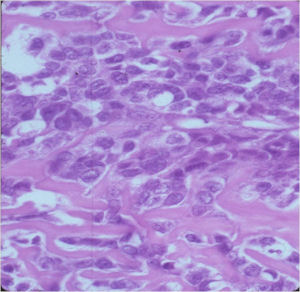

Aggressive Osteoblastoma

- Aggressive osteoblastoma is a distinct rare type of osteoblastoma that has a much more aggressive local behavior than a conventional osteoblastoma. They have a higher chance for local recurrence after removal.

- There has been controversy about the true existence of this type of tumor and whether these tumors are actually low grade osteosarcomas.

- They have a similar appearance microscopically as a conventional osteoblastoma except the osteoblasts are twice as large and have an epithelioid quality with abundant eosinophilic cytoplasm (Epithelioid Osteoblasts).

- Aggressive osteoblastoma is a borderline lesion lesion between osteoblastoma and osteosarcoma. It is not a precursor to osteosarcoma. It does not metastasize.

- Aggressive osteoblastomas usually occur in an older age group than conventional osteoblastoma.

- Most patients are older than age 30. It affects a broad variety of bones.

- Aggressive osteoblastomas are usually larger than a conventional osteoblastoma and have been reported to be up to 8.5 cm in diameter.

- Most have a similar radiographic appearance as a conventional osteoblastoma and have well defined margins, variable amounts of mineralization and peritumoral sclerosis. They occasionally have radiographic characteristics consistent with malignancy.

- Aggressive osteoblastomas are locally aggressive but never metastasize.

The differential between osteoid osteoma, conventional osteoblastoma and aggressive osteoblastoma is based on size and the presence of epithelioid osteoblasts. Can have epithelioid osteoblasts in osteoid osteoma and conventional osteoblastoma but they do not occur in cohesive sheets that fill intertrabecular spaces